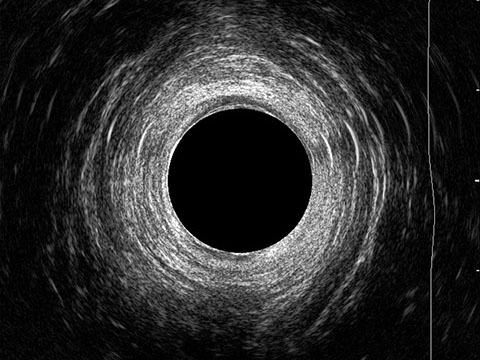

L’ecografia transanale è un esame diagnostico per immagini che consiste nell’introduzione di un trasduttore ad ultrasuoni. Le immagini qualitativamente migliori del canale anale sono ottenute usando un trasduttore rotante, montato in un manipolo rigido, che fornisce un’immagine a 360°. Con le apparecchiature più moderne è anche possibile ottenere immagini tridimensionali.

L’ecografia transanale permette di distinguere la sottomucosa che riveste il canale anale, lo sfintere anale interno, e lo sfintere anale esterno.